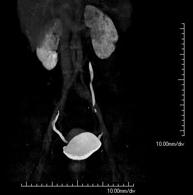

- Colonoscopia virtual  La colonoscopia virtual es una técnica no invasiva que permite la visualización tridimensional y bidimensional del intestino grueso o del colon mediante la toma secuencial de imágenes captadas con TC Multidetector de última generación. La calidad de las imágenes permite la navegación virtual por el interior del recto y del colon gracias al procesamiento en estaciones de trabajo especializadas. La preparación de la prueba consiste en realizar una dieta baja en fibra tres días antes de la prueba (para limpiar el colon y el recto) y de la ingestión de contraste oral yodado el día antes de la prueba (para marcar las heces y poder distinguirlas correctamente de las posibles lesiones colónicas). A diferencia de la fibrocolonoscopia, no se requiere sedación ni soluciones evacuantes. La prueba se realiza en la sala del TC donde, a través de un pequeño tubo flexible, se insufla aire para distender el colon. La colonoscopia virtual es una técnica no invasiva que permite la visualización tridimensional y bidimensional del intestino grueso o del colon mediante la toma secuencial de imágenes captadas con TC Multidetector de última generación. La calidad de las imágenes permite la navegación virtual por el interior del recto y del colon gracias al procesamiento en estaciones de trabajo especializadas. La preparación de la prueba consiste en realizar una dieta baja en fibra tres días antes de la prueba (para limpiar el colon y el recto) y de la ingestión de contraste oral yodado el día antes de la prueba (para marcar las heces y poder distinguirlas correctamente de las posibles lesiones colónicas). A diferencia de la fibrocolonoscopia, no se requiere sedación ni soluciones evacuantes. La prueba se realiza en la sala del TC donde, a través de un pequeño tubo flexible, se insufla aire para distender el colon.